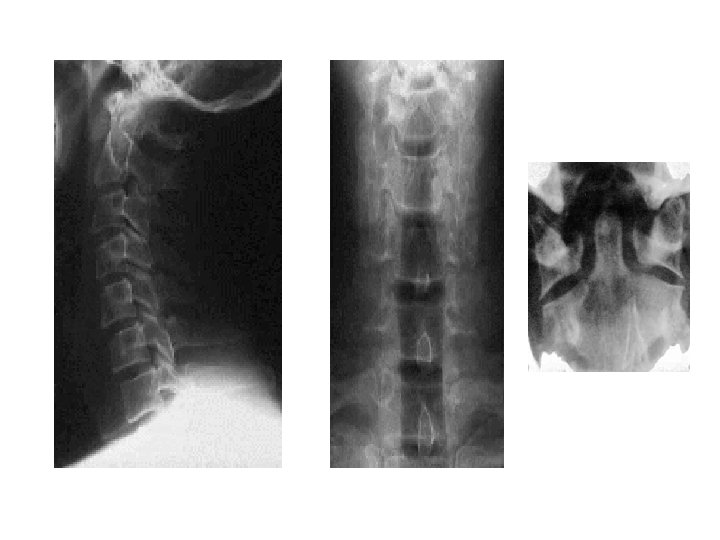

Travmada Acil Radyoloji • Lateral servikal (C 1 -7, T 1) • AP akciğer • AP pelvis * Servikal AP ve odontoid * Yatak başı USG * BBT

C - Servikal fraktür ? • • Multipl travma (düşme, motorlu araç, darp) Klavikula üzeri künt travma Boyun ağrısı olan hastalar Boyun arkasında krepitasyon, deformite Bilinci kapalı hastalar Alkol, ilaç intoksikasyonu Büyük ek yaralanma, fraktürü olan hastalar

Pelvis-Vertebra • Pelviste kırık, kanamayı değerlendir • KÜTÜK ÇEVİRME (3 -4 kişi ile) • Tüm spinöz proseslere dokun Vertebra grafileri Pelvis grafisi